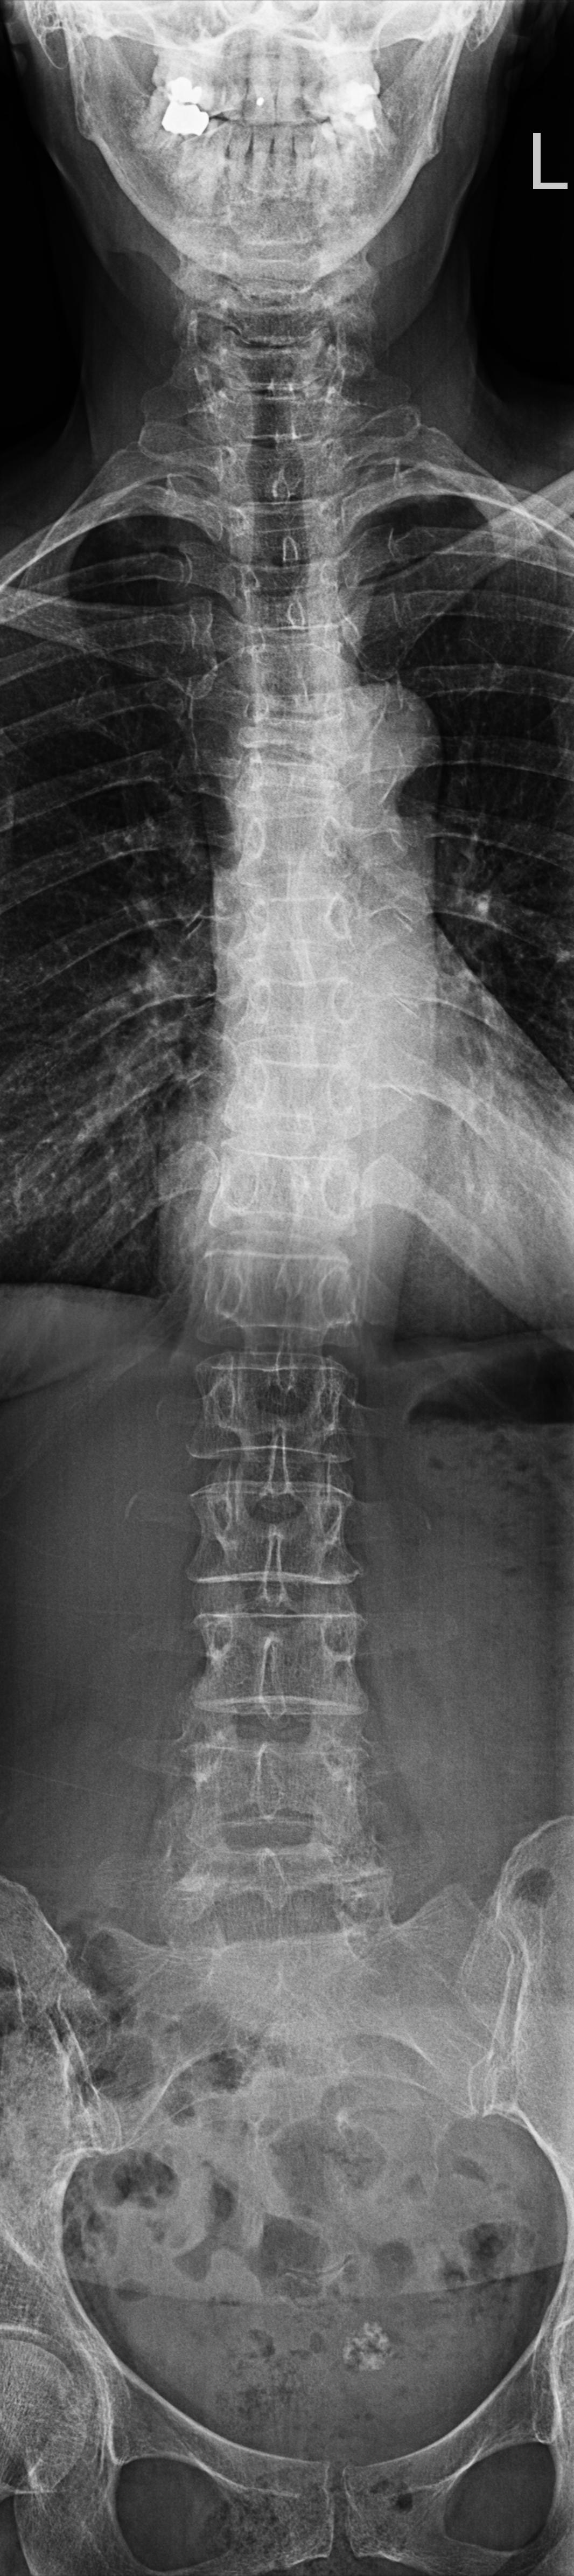

Wirbelsäule Ganzaufnahme a.-p.

Es wurden keine Bilder gefunden.

Technik

• FDA: 3 m

• Ausgangsformat: 3 x 35/43

• mit Raster

Indikation

Beurteilung der Wirbelsäule und des Beckens bei Schiefstand.

Lagerung

Mit dem Rücken am Rasterwandstativ

Kopf leicht nach hinten nehmen

Arme an der Seite

Zentralstrahl

Senkrecht auf Wirbelsäule

Einblendung

von Oberlippe bis einschließlich Hüftköpfe.

Qualitätskriterien

HWS-BWS-LWS mit Sakrum sollte vollständig und gut beurteilbar abgebildet sein.

Anmerkung

Spezialstativ mit Raster oder Digitalaufnahme mit Abbildung eines Rasters zur Vermessung. Evtl Ausgleichschuhe ausziehen und auch ggf. Verlaufsfilter für guten Kontrast verwenden.

Wirbelsäule Ganzaufnahme lateral

Beurteilung der Wirbelsäulestatik, Kyphose und Skoliose.

Mit der Seite am Rasterwandstativ

Kopf in Neutralstellung

Arme nach vorne ausstrecken

Händen kreuzen damit die Schulterblätter rausgezogen werden

von Oberlippe bis einschließlich Hüftköpfe